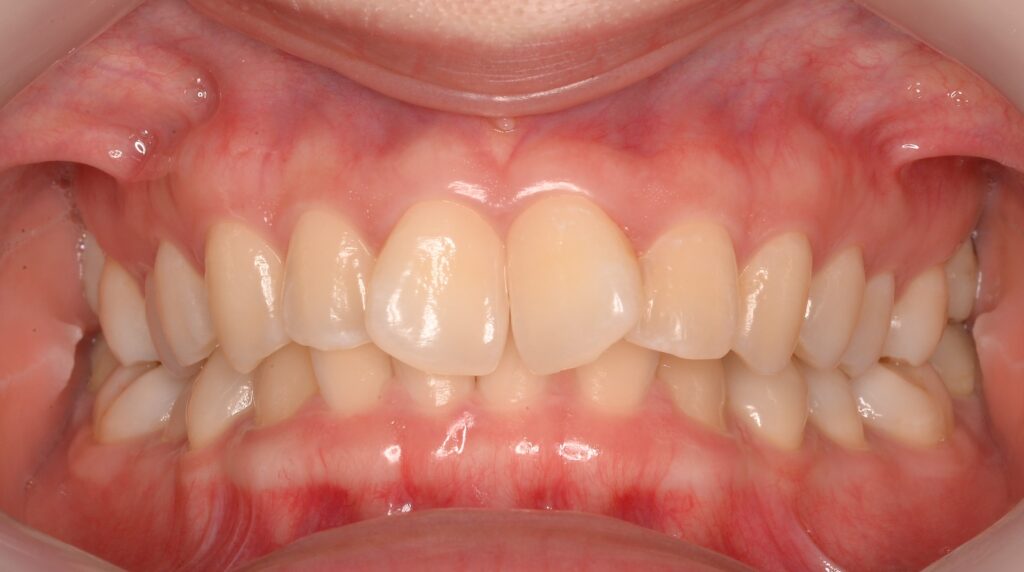

こんにちは!しんデンタルクリニックです🎵 本日は以前から歯並びが気になっていた方のマウスピース矯正の患者様を紹介させて頂きます…more